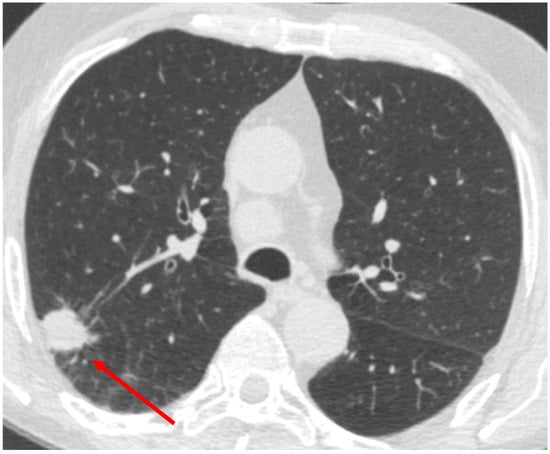

Background: Coccidioidomycosis is an endemic fungal infection in the southwestern United States that can present as solitary lung nodules, mimicking malignancy on imaging. Molecular testing, such as PCR, offers rapid diagnosis but its performance in this clinical setting remains unclear. Methods: We conducted a retrospective analysis of patients evaluated for lung nodules at a tertiary care community-based lung nodule clinic in Central California between 2011 and 2025. Coccidioides PCR in patients with proven or probable Coccidioidomycosis was compared to those with biopsy-proven lung cancer. Diagnostic yield of Coccidioides PCR was assessed across biopsy methods and benchmarked against histology and fungal cultures. Results: Among 122 patients with Coccidioidomycosis, PCR demonstrated low sensitivity (range: 20–41%) but high specificity (100%) across all biopsy modalities. Histology and fungal cultures outperformed PCR, detecting additional cases missed by molecular testing. Notably, 9 PCR-negative cases were confirmed on histology, and PCR was only positive in 71.4% of culture-confirmed cases. Conclusion: Coccidioides PCR testing has high specificity but limited sensitivity for diagnosing lung nodules in endemic regions, limiting its utility as a single test. Histology and fungal culture remain essential. Selective use of PCR may enhance diagnostic efficiency and reduce unnecessary costs in regions burdened by Coccidioidomycosis.

Figure 1